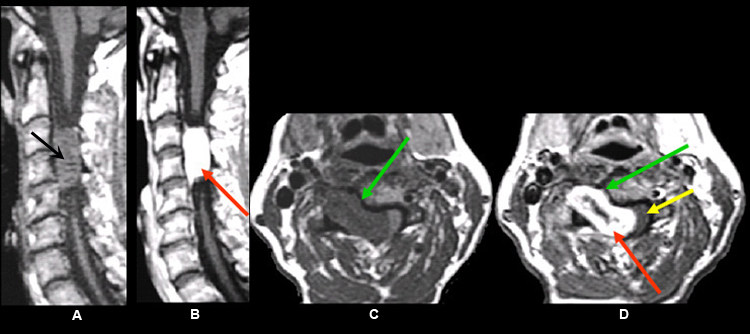

Imaging findings: Figure 2

- Pre-contrast sagittal T1wtd. MRI of the lumbar spine

- bony metastasis (yellow arrow) is seen involving the T12 vertebral body

- Post-contrast (C+) sagittal T1wtd. MRI

- yellow arrow points to the bony metastasis that enhances with contrast

- red arrow points to intramedullay location of metastasis within the distal thoracic cord and showing contrast enhancement

- Sagittal T2 wtd. MRI

- green arrow points to edema within the thoracic cord

- Post-contrast (C+) axial T1wtd. MRI

- red arrow points to intramedullary metastasis

Findings are consistent with vertebral body metastasis and intramedullary metastasis from renal cell carcinoma. |